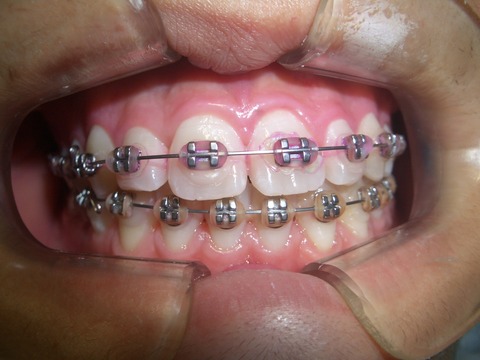

2011.10.5 (1年2ヶ月経過)